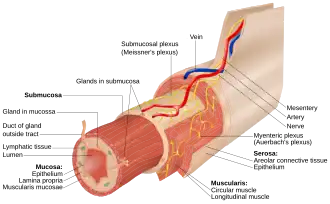

The myenteric plexus (or Auerbach's plexus) provides motor innervation to both layers of the muscular layer of the gut, having both parasympathetic and sympathetic input (although present ganglion cell bodies belong to parasympathetic innervation, fibers from sympathetic innervation also reach the plexus), whereas the submucous plexus provides secretomotor innervation to the mucosa nearest the lumen of the gut.

A part of the enteric nervous system, the myenteric plexus exists between the longitudinal and circular layers of muscularis externa in the gastrointestinal tract. It is found in the muscles of the esophagus, stomach, and intestine.

The ganglia have properties similar to the central nervous system (CNS). These properties include presence of glia, interneurons, a small extracellular space, dense synaptic neuropil, isolation from blood vessels, multiple synaptic mechanisms and multiple neurotransmitters.